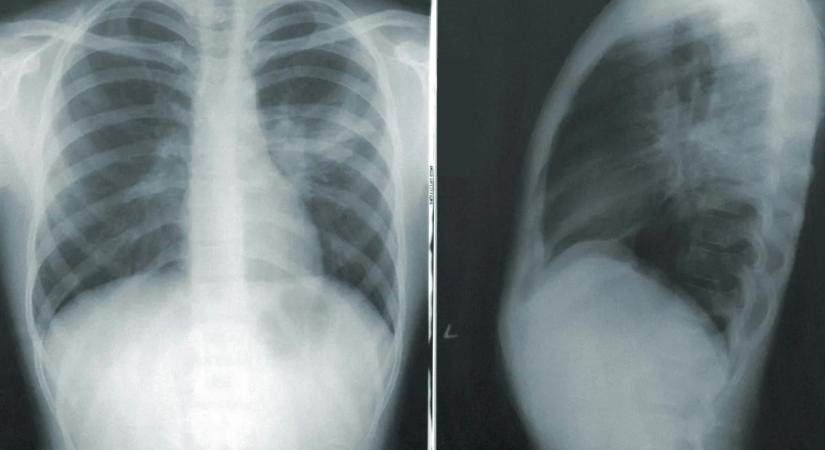

10 Vége a téves diagnózisoknak? Olyat szúrt ki a vérben az AI, ami felett az orvosok simán átsiklottak Kárpátinfo